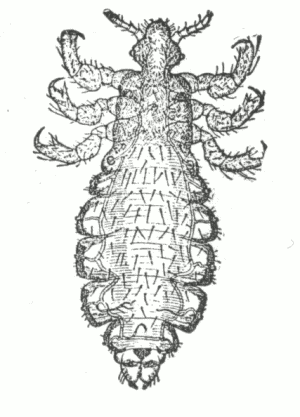

Fig. 11.

Erythema Multiforme, in which many of the lesions have become bullous—

Erythema Bullosum.